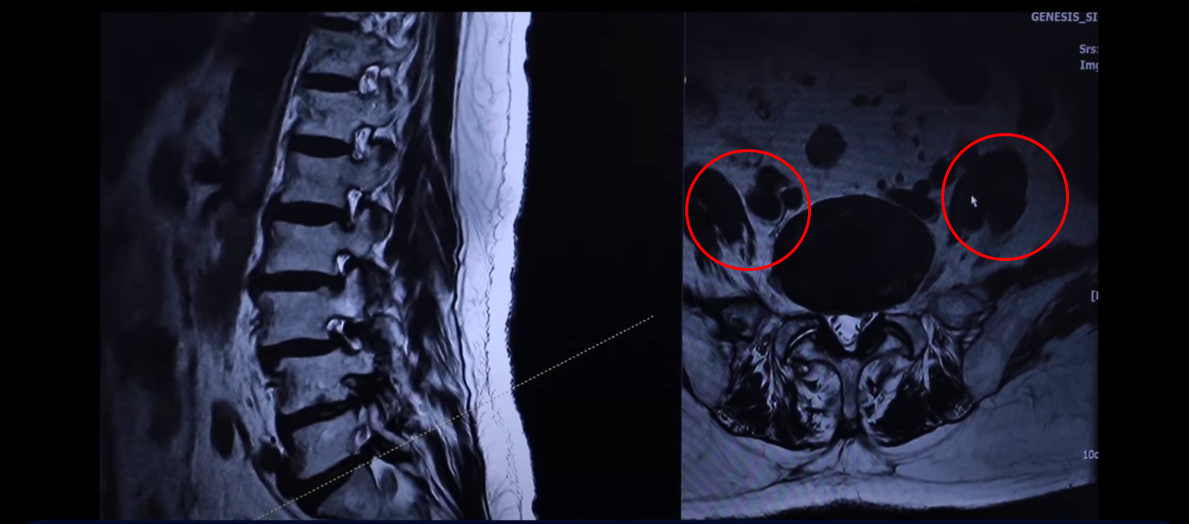

이분 76세 여자 환자분 MRI를 보겠습니다. 이분 MRI를 보시면 보시다시피 허리 여러 마디가 퇴행돼 있고 전방전위가 있습니다. 뼈가 밀려나가 있죠.

그리고 이렇게 뼈가 밀려나간 전방전위증을 가지신 분들은 허리가 오랫동안 아프신 분들이 많습니다. 이분도 한 5년 정도 허리가 아프셨고 그때그때 신경 주사 맞으면서 버티고 사셨는데 신경주사라는 건 맞다 보면 점점 효과가 떨어집니다. 그리고 결국은 다리 증상들이 심하게 생겨서 걷지를 못하게 되시는 거죠. 걷는 거리도 점점 짧아지고 다리는 왜 저리게 되냐면 이분의 이렇게 전방전위증이 있는 마디를 보면 척추관이 좀 좁아져 있지만 아주 많이 좁지 않습니다.

그런데 특히 이 아랫마디 가보면 여기가 많이 좁아져 있습니다. 특히 뭐가 문제냐면 이 척추관보다는 여기 추간공을 보면 이렇게 좁아져 있습니다. 다른 데하고 굉장히 크게 차이가 많이 나죠.

이제 이렇게 환자들이 이런 걸 보시면 아예 까맣게 변해 있다. 신경이 많이 눌리니까 이게 왼쪽 다리로 가는 신경입니다. 그 다음에 오른쪽 다리로 가는 신경을 보면 신경이 여기 지금 까맣게 보입니다. 이 지방이 다 없어져버린 겁니다. 신경 공간이 좁아져 있죠.

그 다음에 이거는 디스크고 이 뒤에 있는 건 황색인대입니다. 이것들이 지금 두꺼워져 있기 때문에 여기 공간이 좁아지는 겁니다. 그래서 이제 오른쪽 다리, 왼쪽 다리가 다 신경이 눌리고 아파서 못 걷는 분입니다.